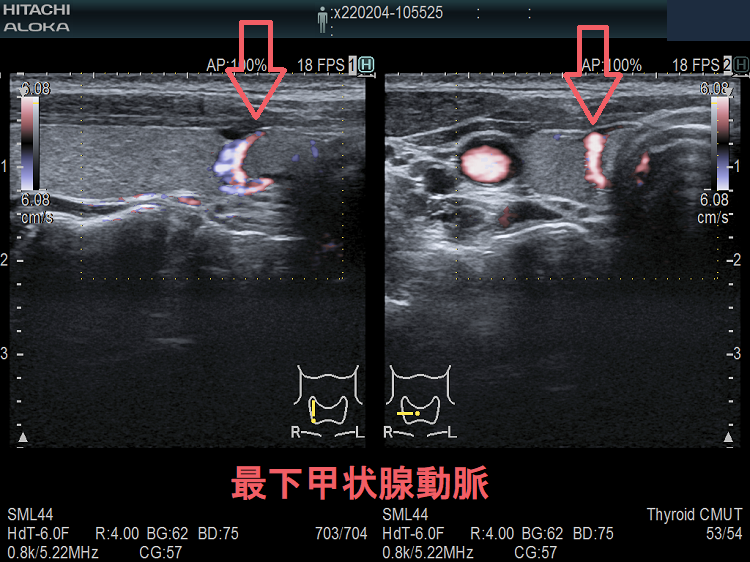

甲状腺穿刺細胞診の主な有害事象の一つは穿刺時出血、穿刺後出血;最悪、気道閉塞により窒息。注意しても唾を飲む方におこる。用手圧迫、再度、超音波エコー、造影CT、喉頭ファイバー行い出血・喉頭腫大を確認後入院。甲状腺機能亢進症/バセドウ病、TSH高値の重度甲状腺機能低下症は甲状腺内部血流が異常増加し穿刺で大出血の危険。甲状腺ホルモン正常化し血流低下を待つ。頚動脈に接する・連鎖して拍動する、下甲状腺動脈直下の小さな甲状腺腫瘍は穿刺難。甲状腺血管腫は何度穿刺細胞診しても血液成分のみで穿刺後出血の危険。最下甲状腺動脈穿刺で大出血。

- 下甲状腺動脈直下で穿刺困難の小さな甲状腺腫瘍